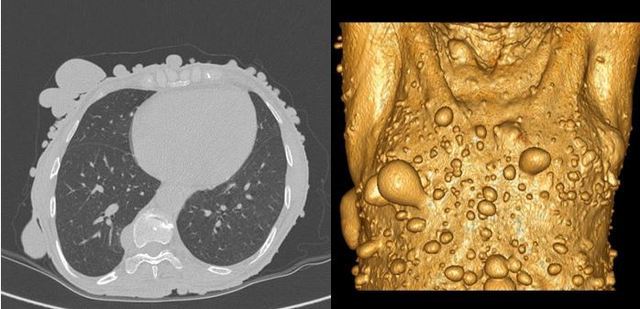

3) CT和MRI:对于脊柱内或颅内的肿瘤可通过CT或MRI检查发现。肿瘤在CT密度通常较脊髓和脑组织略高,呈圆形或类圆形。在MRI上神经纤维瘤表现为T1上低或等信号,T2上高信号。部分肿瘤伴有囊变。增强扫描后肿瘤多明显强化。